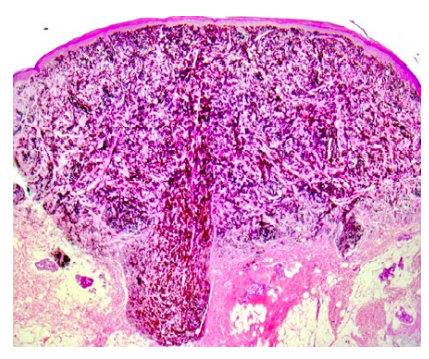

The lesion was promptly excised. Histopathology showed a circumscribed, symmetrical, wedge-shaped dermal proliferation composed predominantly of pigmented epithelioid cells and dendritic cells. The cells had large nuclei and prominent nucleoli. In some areas multinucleated cells were found. No mitotic figures were identified.

Figure 2: Symmetrical, wedge-shaped dermal proliferation composed predominantly of pigmented epithelioid and dendritic cells (H&E x100).